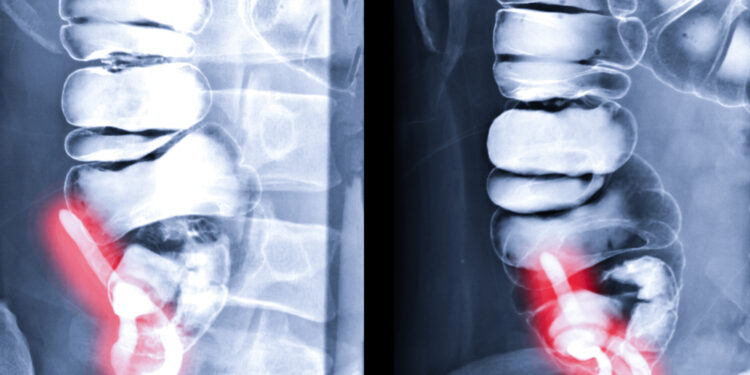

Bario klizma – tai diagnostinis radiologinis tyrimas, kurio metu naudojami rentgeno spinduliai ir speciali kontrastinė medžiaga, siekiant detaliai apžiūrėti storąją žarną. Šis tyrimas taip pat žinomas kaip apatinės virškinimo trakto rentgenograma, kolonos rentgenas ar apatinės virškinimo sistemos tyrimas.

Atliekant tyrimą naudojamas rentgeno aparatas, vadinamas fluoroskopu, kuris leidžia vaizdą matyti realiu laiku. Procedūros metu į žarnyną specialia žarna suleidžiamas baltas, tirštas baris – ši medžiaga padeda aiškiau matyti žarnyno sienelę, formą ir dydį. Kai kuriais atvejais per tą patį vamzdelį gali būti suleista oro – tuomet atliekama vadinamoji dvigubo kontrasto bario klizma.